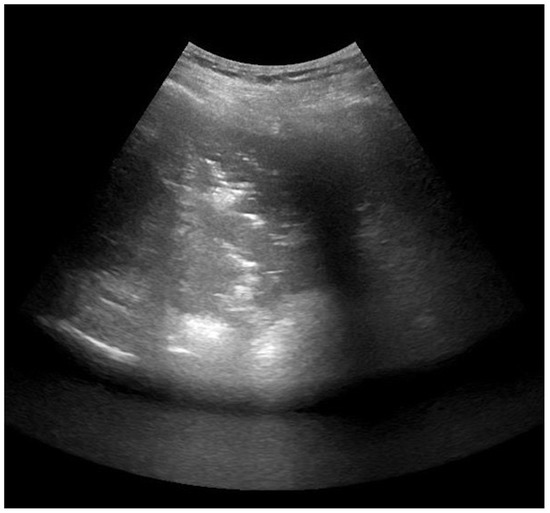

:1. Introduction

2.1. Study Design

2.4. Lung Ultrasonography and Score Assessment